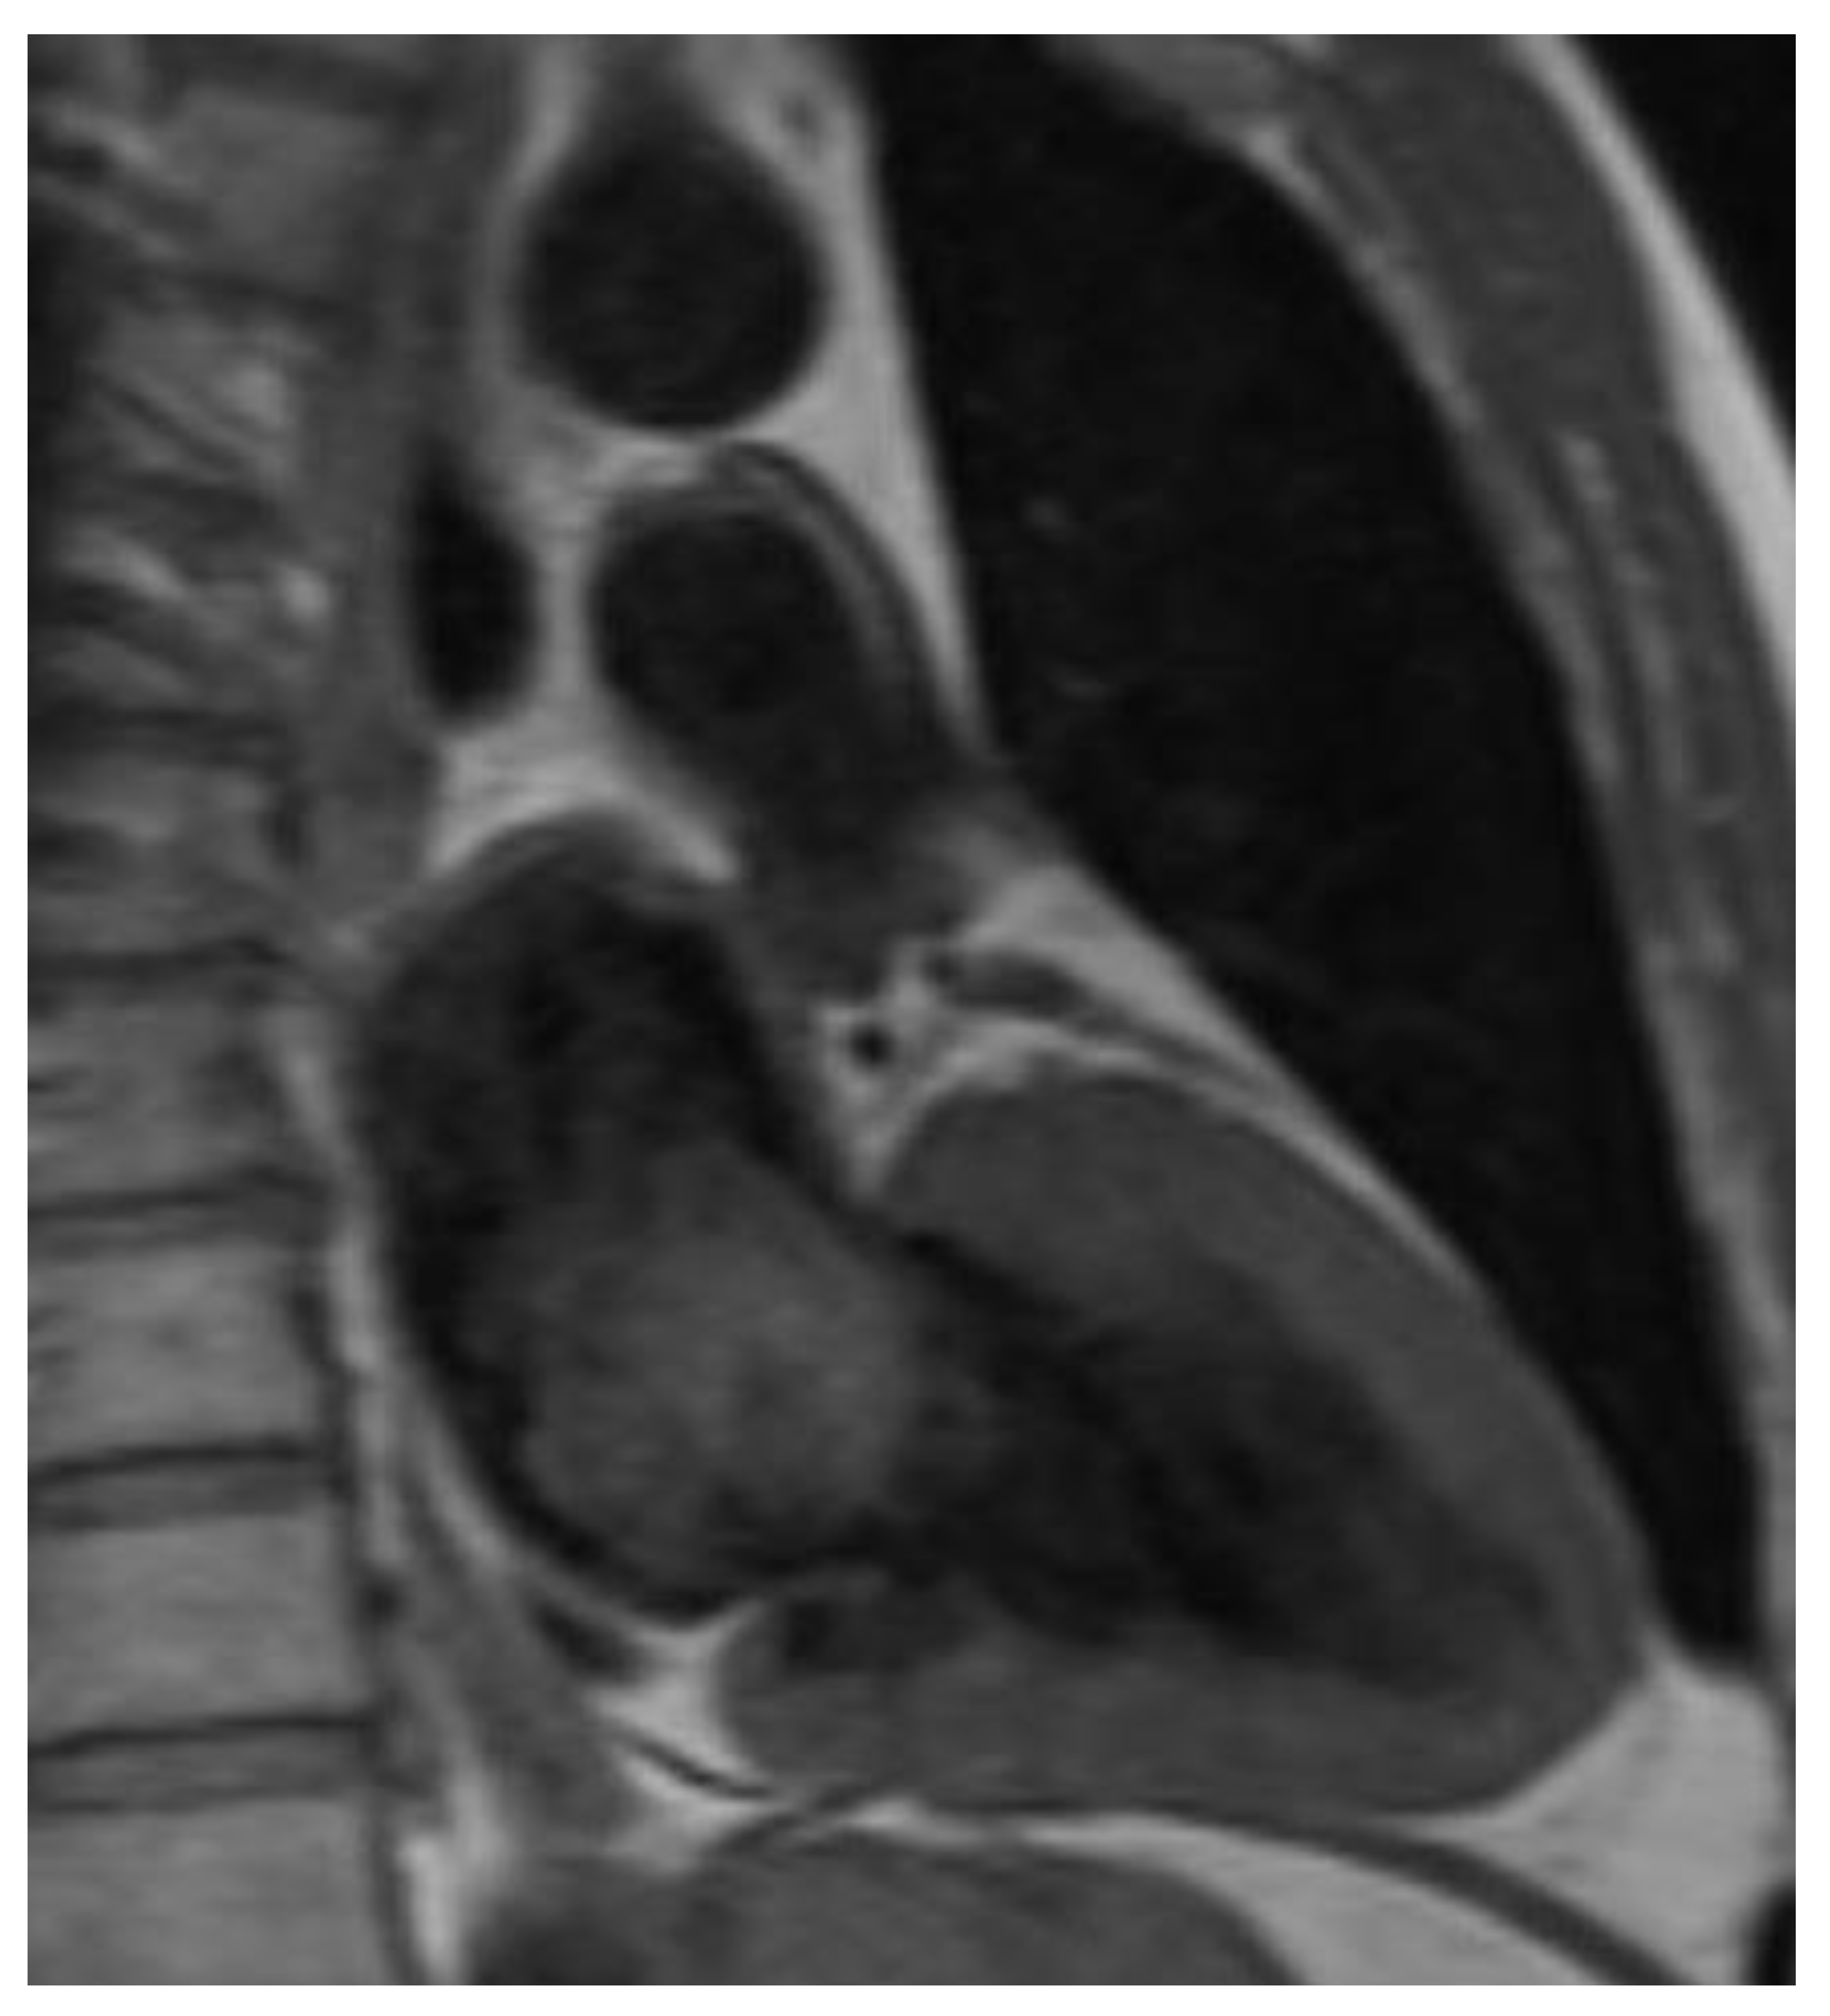

Cardiac Myxomas Resembling Malignant Neoplasia: Incidentally Diagnosed vs. Cerebral Embolized Myxomas

| Magnetic resonance imaging (%) | 7.1 | 13.5 | 1.000 |